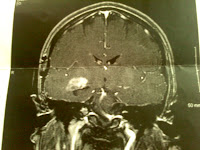

This afternoon we found out that my tumor is the same grade and type as it was the last time they got some pieces of it onto a slide. It's a "pleomorphic xanthoastrocytoma" (PXA) and it's a grade II on the WHO-scale. This is GOOD NEWS as far as my situation goes becuase PXAs can morph into a higher (more serious and aggressive) grades, as was a concern from my January MRI.